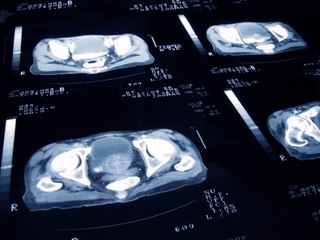

Tumore alla prostata sintomi, ecco quelli da non sottovalutare